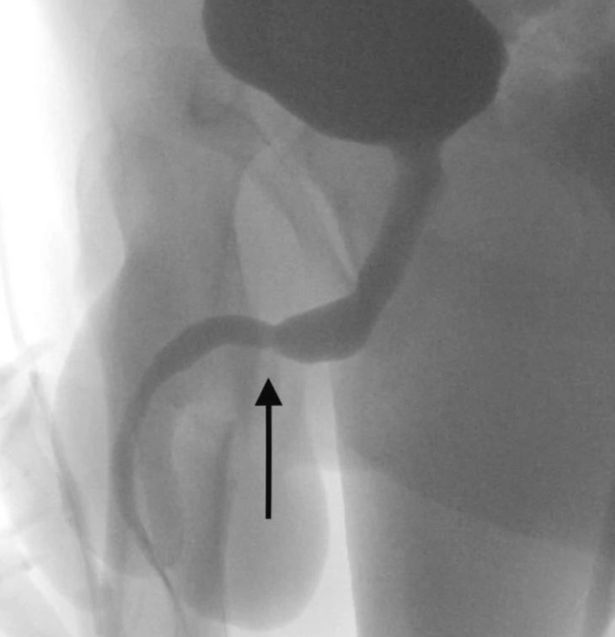

Pasi u krye një rreze X që zbuloi madhësinë dhe pozicionet e sakta të fishës, adoleshenti u dërgua në kirurgji. Nuk kishte komplikime gjatë operacioniet dhe adoleshenti u lirua nga spitali të nesërmen.